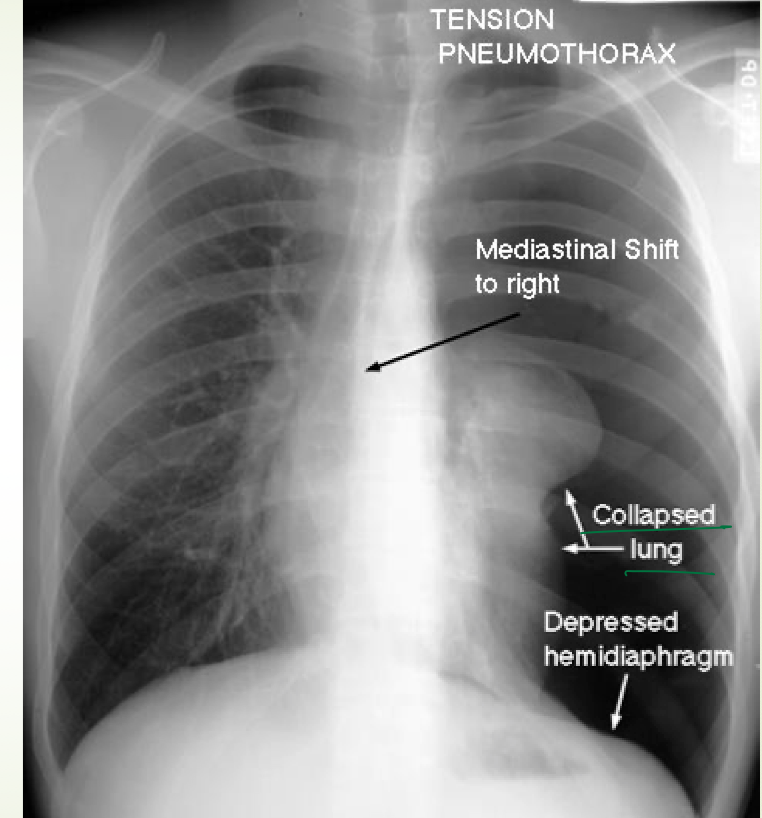

what is tension ptx

when pleural pressure exceeds atmospheric pressure leading to decreased venous return and decreased cardiac output

how does tension pneumothorax contribute to obstructive shock

because it decreases venous return –> decreases Cardiac output –> decreases BP CAUSES OBSTRUCTIVE SHOCK

you will tracheal deviation to the ____ side in a tension pneumothorax

contralateral.

management of tension pneumo

this is a medical emergency

Medical emergency!!!

• Decompression!!!

• Large bore needle 2nd intercostal space, mid clavicular line

• Chest tube + water seal